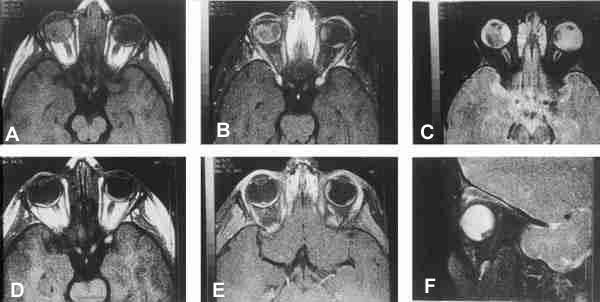

25-03.jpg (32572 bytes)

Figuras 3a, b, c, d, e y f. Retinoblastoma bilateral.

Secuencias potenciadas en T1 pre y post la administración de gadolínio, y potenciadas en T2 (a, b, c). RM de control 11 meses después de finalizar el tratamiento (d, e, f).

Marcada disminución de tamaño de las masas (d, e) respecto al primer estudio (a, b), aunque con persistencia de captación de contraste.